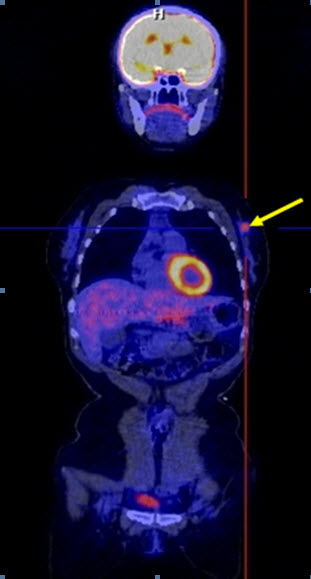

Hình 4 (a, b) cho thấy giá trị của PET/CT trong đánh giá giai đoạn của ung thư vú. Bệnh nhân Nguyễn Th. T. Tr., nữ, 63 tuổi, chẩn đoán là ung thư vú. Kết quả PET/CT toàn thân cho thấy nhiều tổn thương di căn hạch cổ, hạch trung thất, di căn 2 phổi, gan, xương tăng hấp thu FDG.

Hình 4a. Hình PET toàn thân thấy nhiều tổn thương hạch cổ, hạch trung thất (mũi tên vàng), phổi (mũi tên đỏ), gan (mũi tên tím) và xương (mũi tên xanh) tăng hấp thu FDG.

Hình 4b. Hình PET/CT ở mặt phẳng cắt ngang thấy tổn thương di căn phổi (mũi tên đỏ) và di căn gan (mũi tên da cam).